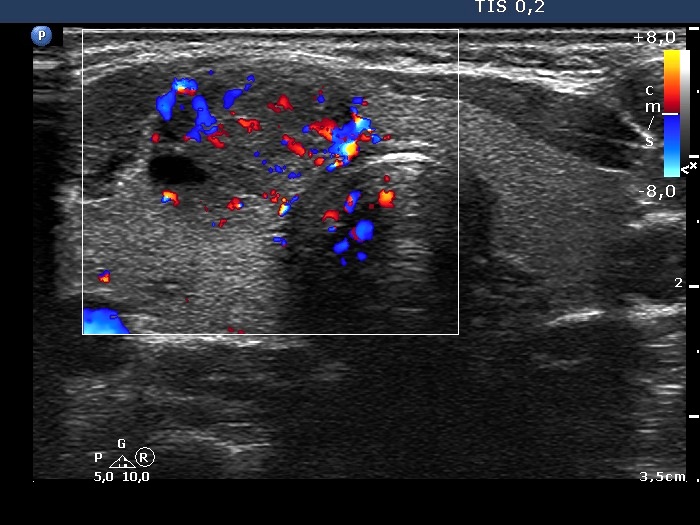

First examination (first row of images):

Clinical presentation: A 31-year-old woman was referred for evaluation of a nodule discovered by herself.

Palpation: a not firm nodule in the isthmus.

Hormonal evaluation: euthyroidism with TSH 0.75 mIU/L.

Ultrasonography. The thyroid was echonormal. There was a small, moderately hypoechogenic lesion in the lower part of the left lobe while a larger nodular area was located in the isthmus. The latter was composed of hypoechogenic and echonormal parts and presented cystic degeneration, as well.

Aspiration cytology of the isthmic nodule disclosed a follicular lesion with signs of hyperthyroidism.

We indicated scintigraphy which revealed an autonomously functioning nodule according to the lesion in the isthmus. We suggested follow-up, yearly TSH determination.